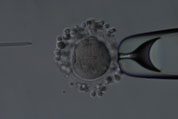

Intracytoplasmic Sperm Injection, more commonly known as ICSI, is a technique that involves the injection of a single sperm into an egg. For couples with severe male factor infertility or couples with prior In Vitro Fertilization attempts in which failure to fertilize occurred, ICSI has proved to be successful. In cases where the sperm must be taken directly from the testes, ICSI will be used to achieve fertilization. The procedure involves the processing of sperm from a semen specimen or testicular biopsy. A single live sperm is then injected directly into egg with a glass needle. The fertilization and pregnancy rates are comparable to those seen with IVF couples with no male factor infertility problems.